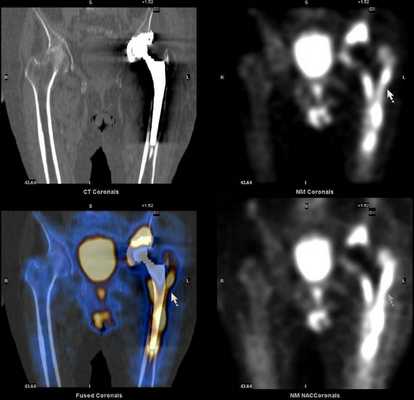

Остеосцинтиграфия в ортопедии и вертебрологии

При протезировании суставов или установке металлоконструкций в позвоночник сцинтиграфия костей скелета позволяет достоверно выявить:

- механическую нестабильность компонентов протеза (расшатывание)

- воспалительный процесс вокруг протеза или металлоконструкции

- интенсивность протекания воспалительного процесса в различных участках кости.

Дополнительное проведение ОФЭКТ/КТ с возможностью посрезового анализа изображения, позволяет более точно локализовать область повреждения, что дает возможность своевременно провести необходимое лечение.

Преимущества ОФЭКТ/КТ по сравнению с планарной сцинтиграфией: отсутствие суммации (посрезовый анализ накопления радиофармпрепарата) и точная локализация благодаря совмещению радионуклидного и КТ-изображений.